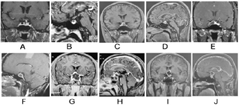

注:A、B:Rathke囊肿;C、D:垂体瘤囊变;E、F:垂体卒中;G、H:垂体脓肿;I、J:颅咽管瘤

Rathke囊肿大多数病变位于鞍内或者鞍内及鞍上,极少数位于鞍上[4]。在影像学上,大多数界线清晰、信号均匀、圆形或椭圆形、单发囊,垂体受压但可见,通常蝶鞍不会出现破坏或扩大,囊肿压迫周围组织产生炎症或垂体受压时可引发囊壁强化(图1A、B)。CT及MRI因囊液内的成分不同,密度或信号常高低不等。CT扫描中,Rathke囊肿多表现为边界清楚的圆形或类圆形低密度占位,而在囊液内蛋白含量较高时,相应表现为等或高密度。MRI扫描对Rathke囊肿的诊断价值明显优于CT[11,26,27,28]。Rathke囊肿在MRI上的信号呈多样,T1WI信号高、等、低信号均存在,以高信号多见,而T2WI以高信号为主,少部分为等或低信号。囊肿内不同成分如黏多糖、蛋白质、胆固醇、坏死细胞碎片和含铁血黄素等构成了其信号复杂的原因[4]。文献报告MRI检查时37.5%~45%的病例囊肿内可见TWI低信号的结节影,这种囊内结节在确定Rathke囊肿的诊断中具有重要价值[29,30],结节主要由蛋白质、胆固醇和细胞碎屑堆积而成,增强扫描时不强化。另外,囊内分层且不会随体位变化改变现象也是RCC相对特征性表现,有助于与垂体腺瘤出血、囊变等鉴别[31]。

垂体MRI常显示垂体大腺瘤的表现,但有囊性变(图1C、D)。其直径多>2 cm,常向上突破鞍膈出现"束腰征"或"雪人征",囊腔常偏离中线,蝶鞍常有扩大,侵袭性垂体腺瘤常侵及海绵窦段颈内动脉,此外,蝶窦与斜坡可有不同程度受侵。囊壁T1WI与T2WI序列均为等信号多见,囊壁常厚薄不均,增强扫面时囊壁及未囊变的瘤体明显强化;囊液部分以T1WI低信号或稍低信号、T2WI高信号或稍高信号为主[4],并出血时T1WI可以出现高信号,增强后无强化;出血时囊内可见分层,且分层现象随体位改变而变化[15]。

因垂体卒中大多数发生在垂体大腺瘤患者,因此其MRI特点大多与垂体瘤囊变的影像学特征类似(图1E、F),但由于垂体卒中多为急性出血,除了临床表现严重外,核磁信号因出血时相不同表现多样[17,32],急性期T1WI等信号或稍高信号,T2WI低信号,亚急性期(7~21天)由于存在高铁血红蛋白,T1WI和T2WI为高信号,晚期周边可出现强化,通常被称为"垂体环征",慢性期(>21天),由于含铁血黄素和铁蛋白,T1WI和T2WI为低信号。囊内可见分层,且分层现象随体位改变而变化。

垂体脓肿的CT表现为鞍内低密度病变,囊壁多无钙化,增强呈明显环状强化。MRI主要表现:鞍内占位为主,可以向鞍上扩展,呈圆形、椭圆形或葫芦型的囊实性肿物,有时存在分隔,一般直径在3.0 cm以下,垂体柄可以增粗,囊液T1WI呈低或等信号,T2WI呈等高信号或混杂信号,信号高低与出血和坏死液中蛋白含量有关,多数边界不清楚,病灶边缘信号较高,增强后不均匀环形强化,可见分隔状强化的囊状影,且常常可见临近的脑膜或海绵窦强化[33](图1G、H)。垂体脓肿在弥散加权成像(DWI)上表现为高信号[22],ADC低信号,垂体瘤坏死囊变则恰好相反,有助于两者的鉴别诊断。

影像学在颅咽管瘤诊断中具有重要价值。病变多数位于鞍上(75%)或同时累及鞍内与鞍上,仅位于鞍内的临床罕见。鞍上部分常压迫第三脑室使其变形或移位,垂体多受压,鞍底多无下陷,病变(图1I、J)呈囊性、囊实混合型或实性,常呈分叶状、类圆形,囊壁不规则增厚(>2 mm),约75%存在一个或多个囊腔。囊液信号最常见为T1WI低信号、T2WI高信号,但囊内蛋白含量高时可以表现为T1高信号,T2等或低信号,波谱可见宽大脂峰,囊内可出现分层现象,但不随体位而改变;囊壁在T1WI与T2WI主要呈等信号,实性部分不均匀强化,其中部分为环状强化[4]。钙化为颅咽管瘤常见表现,60%~80%的颅咽管瘤患者可见鞍上区钙化[9],CT表现为周围弧形的高密度影,或称"蛋壳样钙化",为其较为特征性表现。